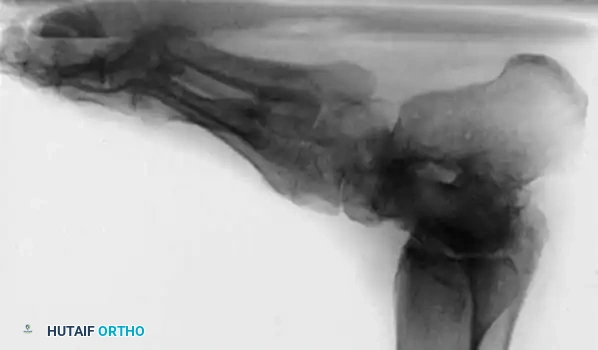

Radiographic Evaluation

Brockway’s 1940 axiom remains true: "Cavus feet should never be operated upon until radiographs with the patient standing have been taken."

Standard weight-bearing anteroposterior (AP) and lateral radiographs of the foot, along with a weight-bearing AP of the ankle, are required.

Key Radiographic Parameters:

* Meary’s Angle (Talus-First Metatarsal Angle): Normally 0 degrees. In a cavus foot, the angle is convex upward (apex dorsal), indicating midfoot/forefoot equinus.

* Calcaneal Pitch: Normally 15 to 20 degrees. In a cavus foot, it is significantly increased (>30 degrees).

* Hibbs Angle: The angle between the longitudinal axis of the calcaneus and the first metatarsal. It approaches 90 degrees in severe cavus (normal is ~140 degrees).

* Talonavicular Coverage: Assessed on the AP view to quantify midfoot adduction.

Fig. 7: Standing lateral radiograph demonstrating an increased calcaneal pitch and a severe apex-dorsal Meary's angle.